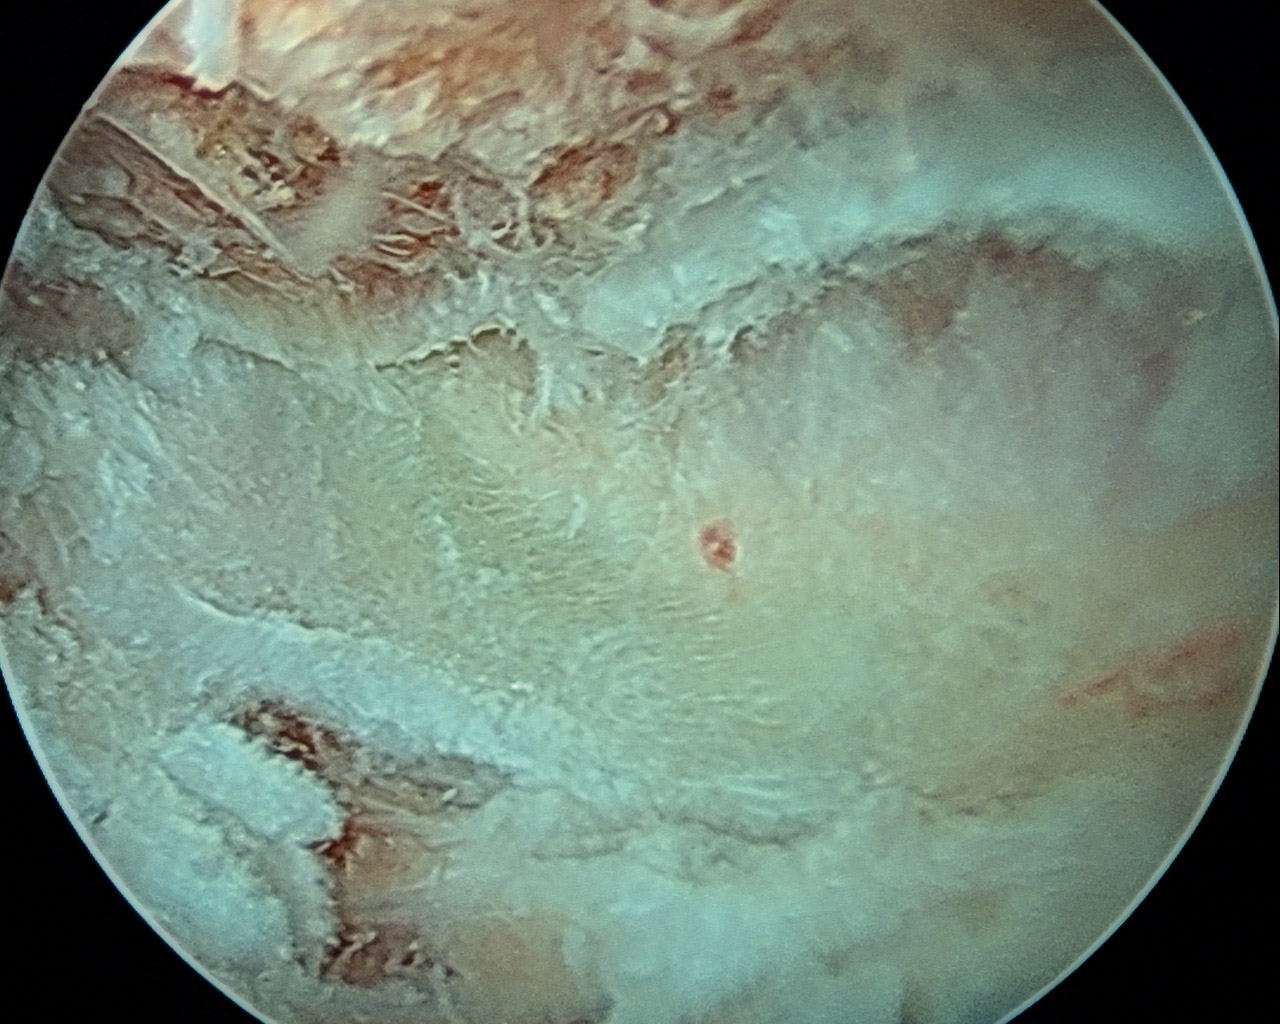

Se practicó una técnica de 2 portales (superior e inferior), estableciéndose como portal de inicio, para introducir el artroscopio con óptica de 30°, el portal inferior, que es el portal de visión, localizado 3-4 cm medial al borde medial de la escápula, en el punto medio entre la espina y el ángulo inferior. El portal superior, o portal de trabajo, se realizó mediante visión directa con ayuda de una aguja al nivel de la espina y también a 3-4 cm del borde medial (Figuras 2 y 3).

A través del portal de trabajo y con ayuda de sinoviotomo y radiofrecuencia, se procedió a la extirpación del tejido fibroso y bursal para exponer el ángulo superomedial de la escápula, localizado mediante palpación directa y la movilización indirecta de la escápula al mover el brazo (Figura 4).